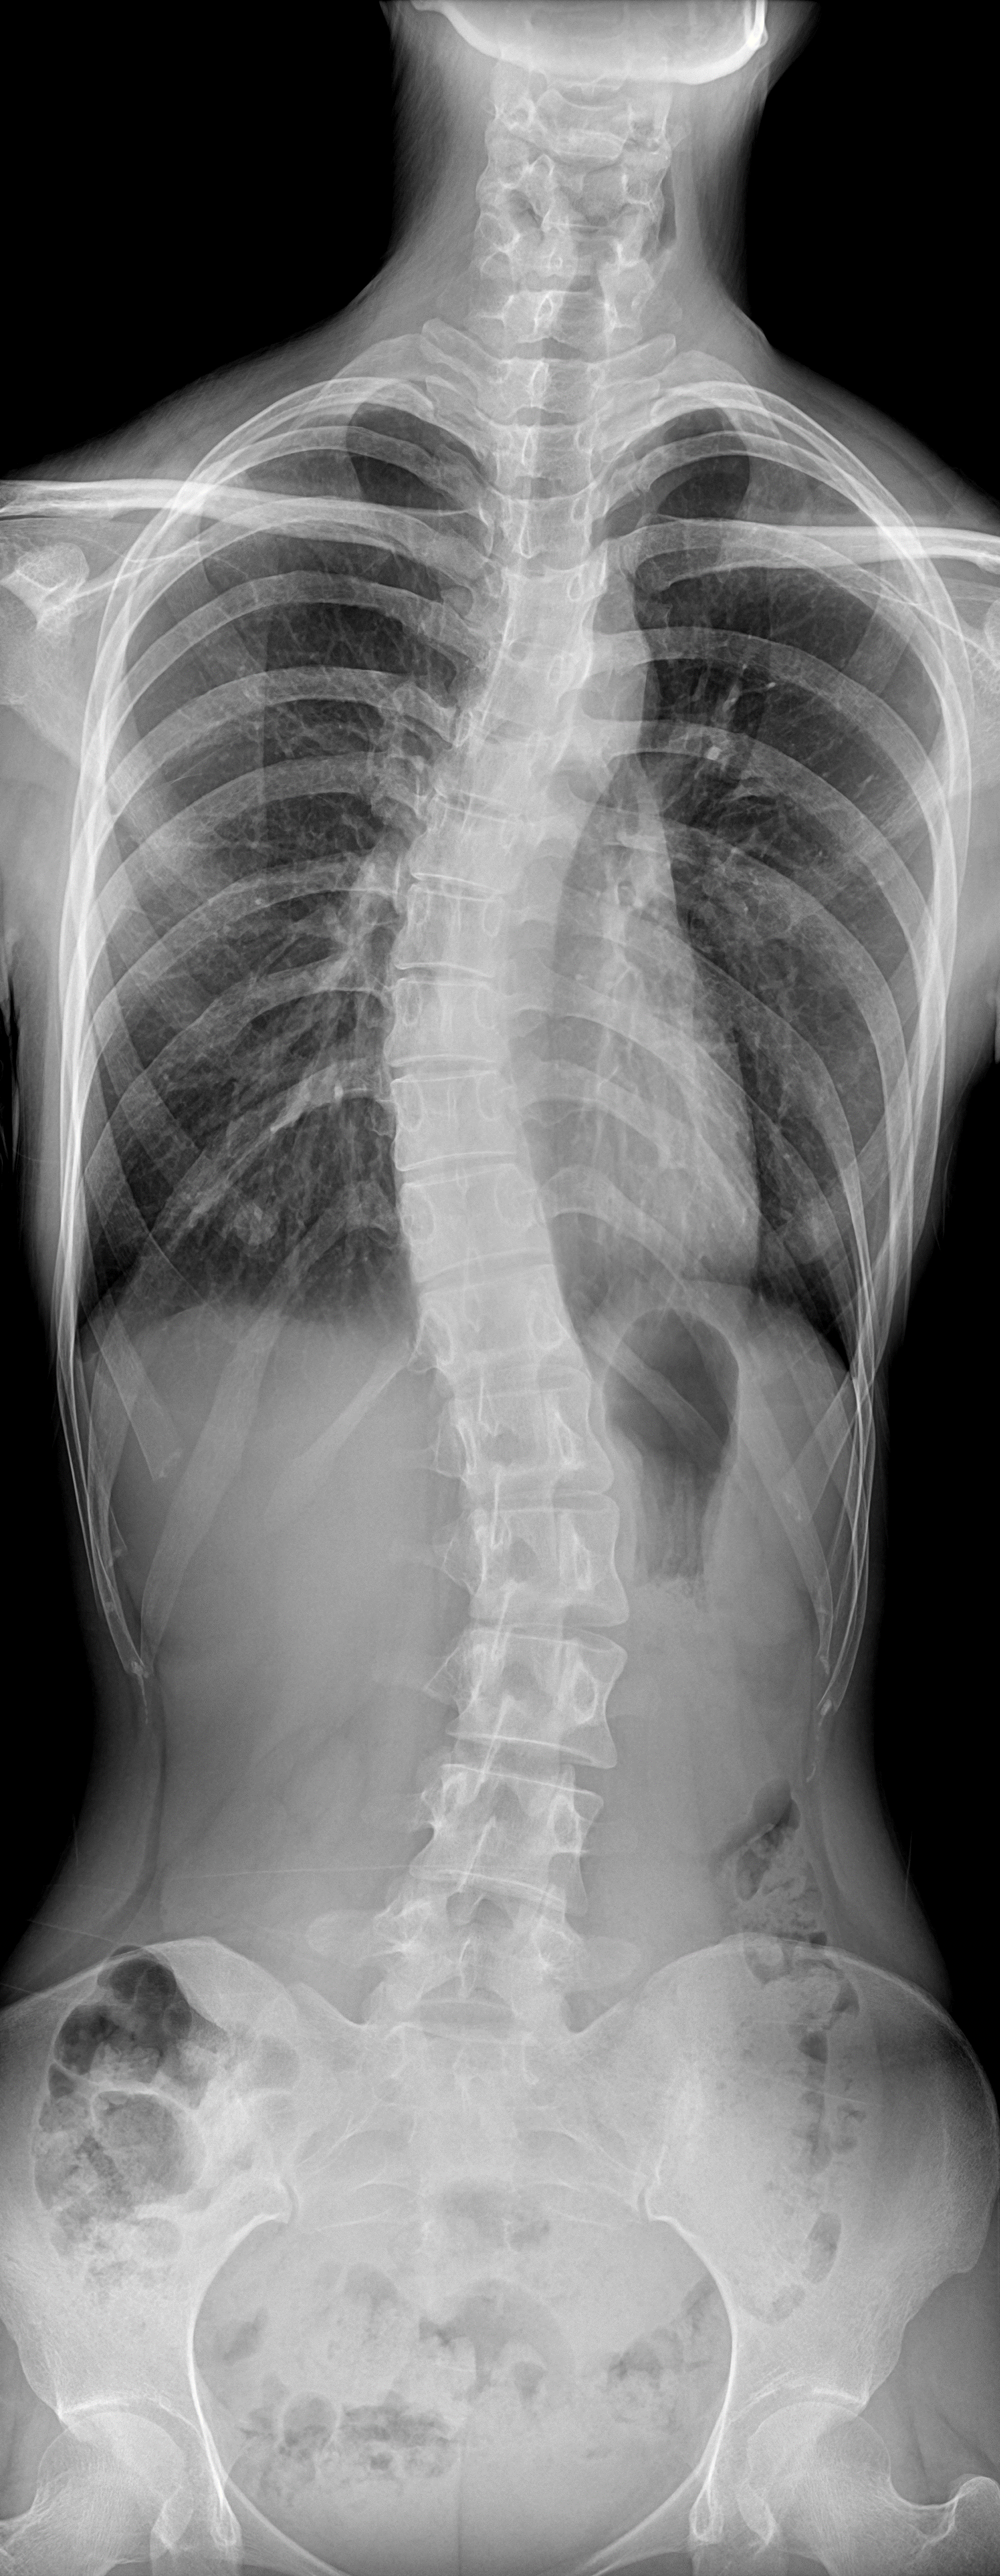

作为国产第一台超高端悬吊动态 DR,珠穆在机械运动设计上采用了 4D 十轴运动系统,机架运动自如平稳,配合电动升降床及多功能式摄影架,探测器与球管双向自动跟踪,立位与卧位一键切换、一键到位,满足临床各种体位摄片需求,拍摄效率相较于一般悬吊 DR 来说,更快更好更智能。拿骨科为例,现在医院的骨科脊柱侧弯或下肢置换手术的患者比较多,珠穆支持全自动全身影像拼接功能,可以为骨科关节置换、脊柱矫形等手术提供全下肢或全脊柱拼接影像,利于术前方案制订及术后效果评估。

同时,这款产品搭载了 2 块平板探测器,包含一块动态平板探测器与一块静态平板探测器。既可以满足日常拍片,也可以进行可视化点片检查。其中,动态探测器采用 17 * 17 大幅面设计,拥有 960 万的高清像素,可以实现 0.8S 快速动静态切换点片,动态观察特别是对于重叠性的部位包括肋骨或锁骨的结节识别,都有非常精准的评估价值。在动态观察过程中,还支持局部放大功能,对于一些微小的病灶可以更清楚的显示,对于以往那些不好甄别的病灶,能够更加清楚的显示。这款珠穆悬吊式动态 DR 的影像链从高压发生器、球管、探测器、机架、软件处理工作站,都包含了安健科技自研的专利技术,可以保证非常优质稳定的 X 射线输出,应对大流量的患者拍摄。